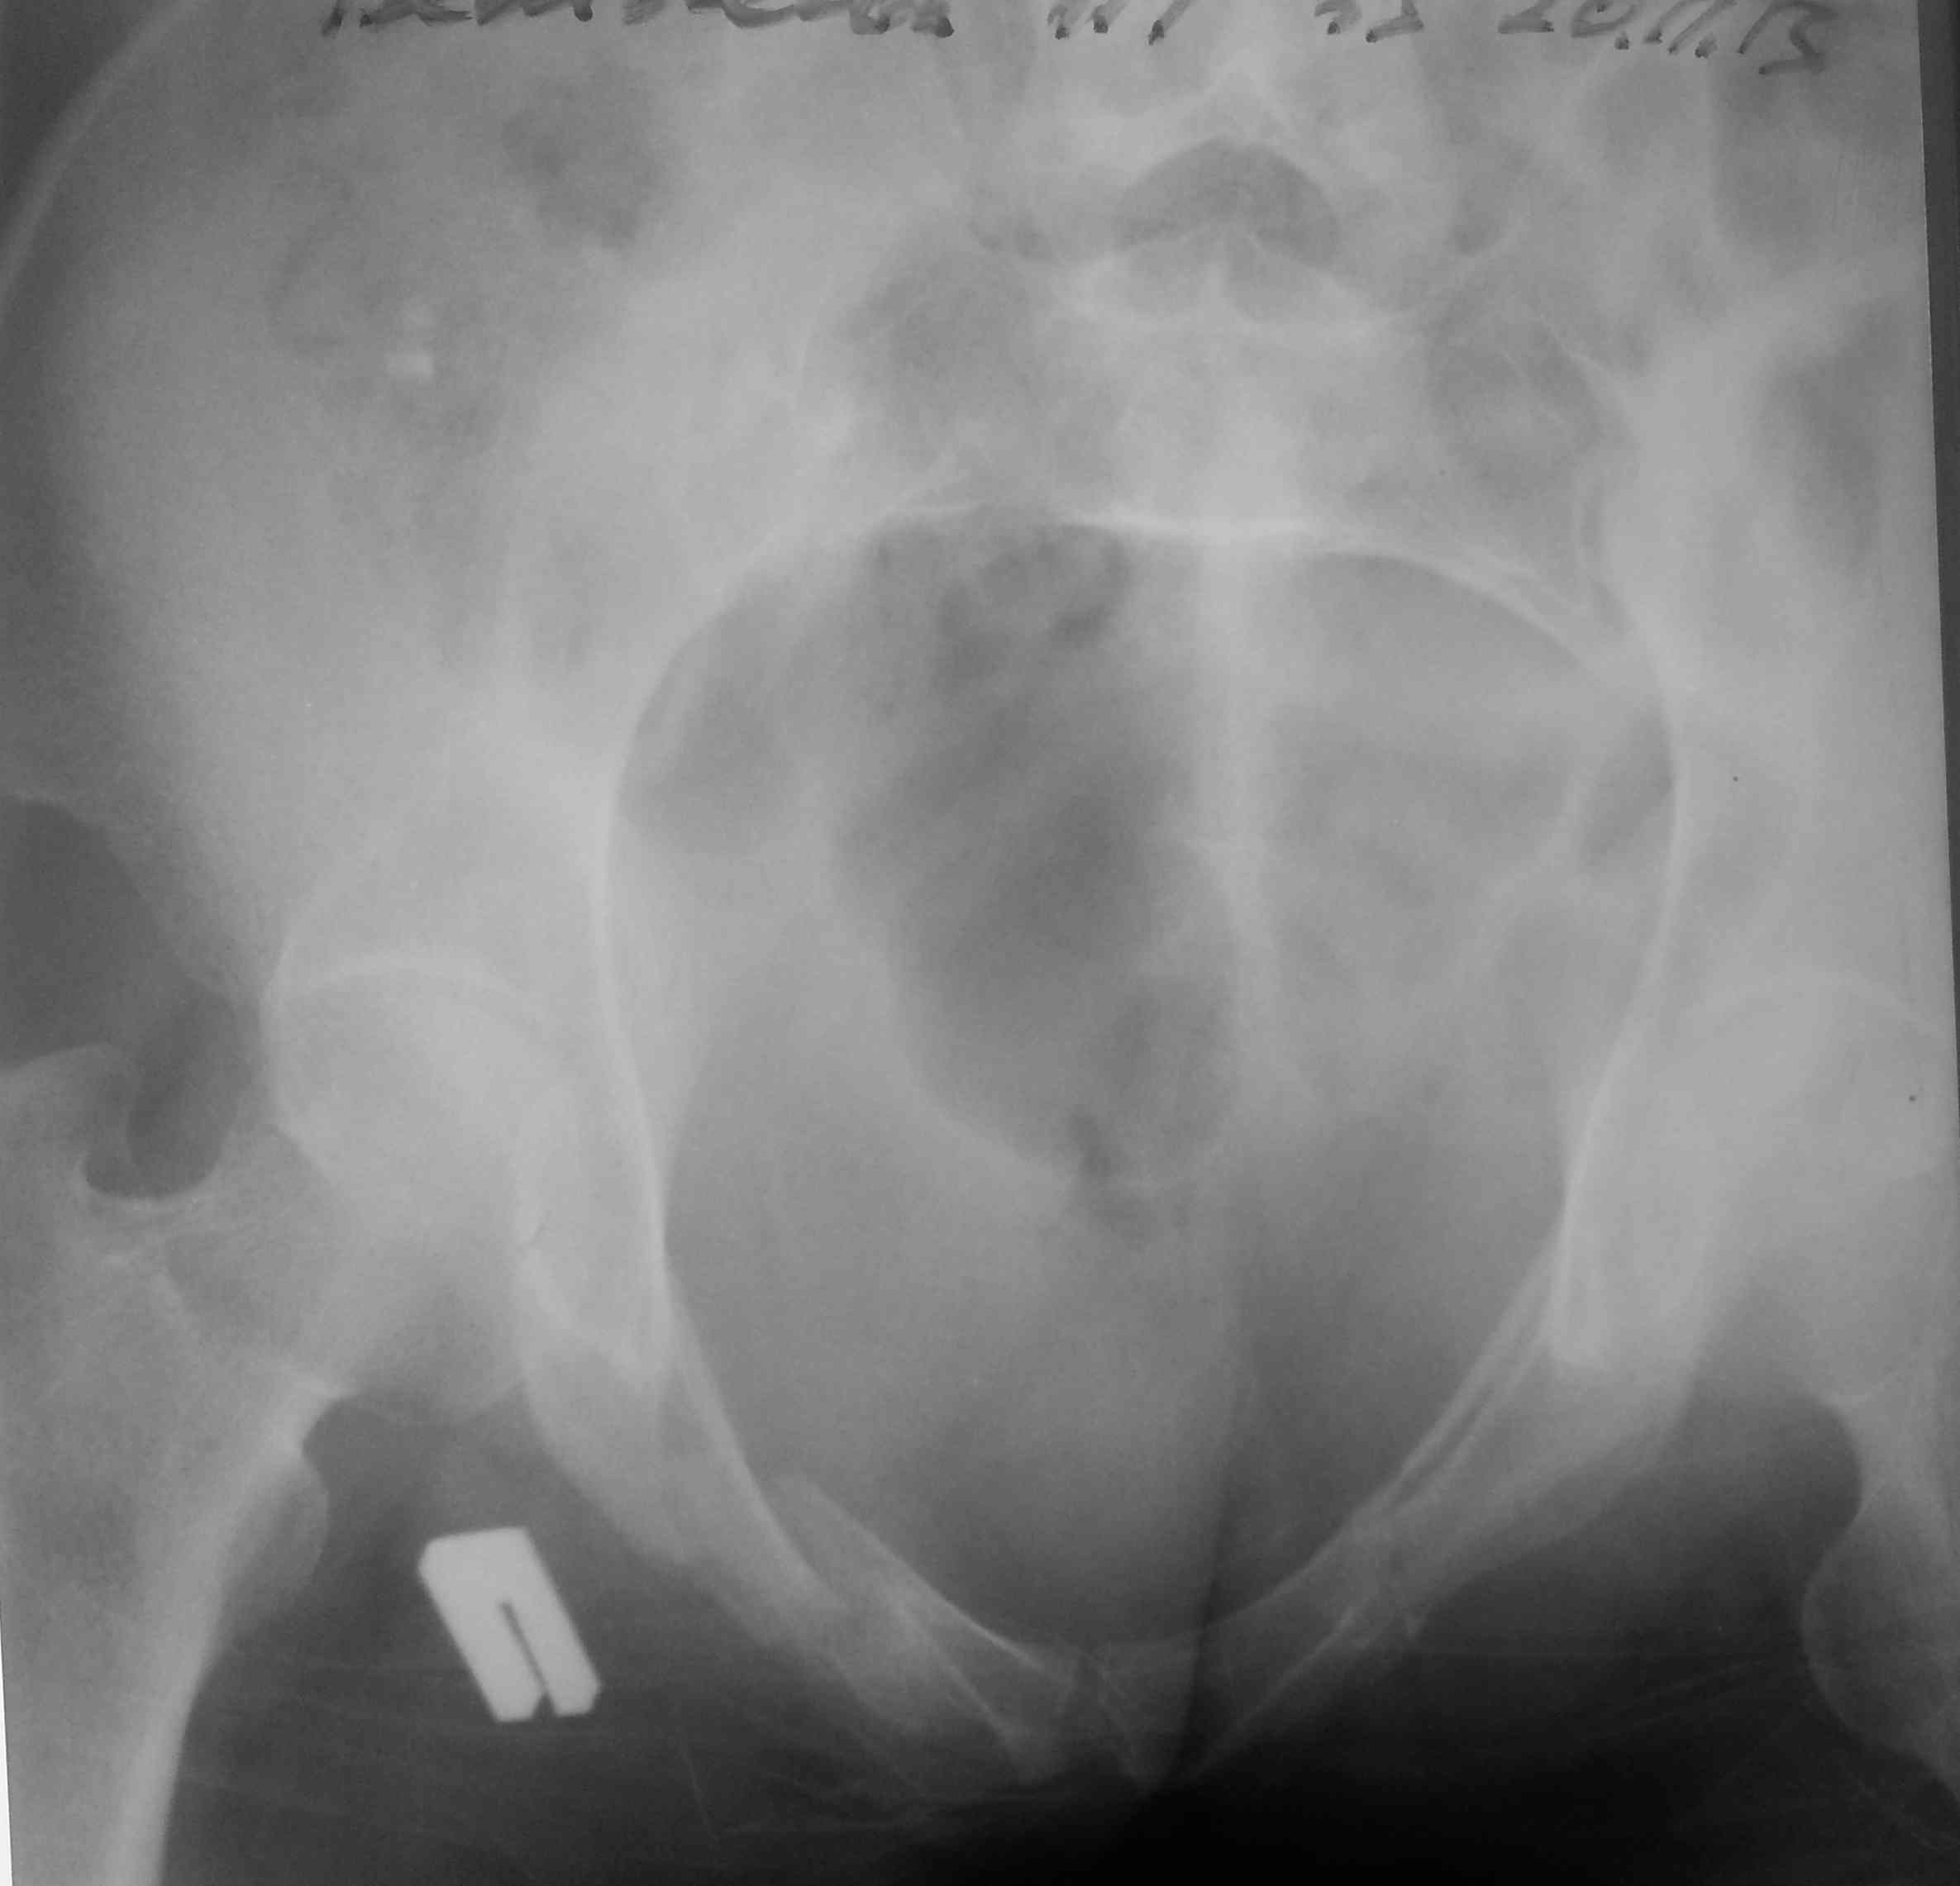

высылаю контрольные снимки на вытяжении, правую половину таза подрепонировали вручную, за лево - скелетка. Дополнительно, левое плечо - диафиз, множественные переломы ребер слева. Стала хуже по легким. Пока план - при улучшении по легким - передняя рама + илиосакральные винты справа, при улучшении - расслабляем переднюю раму, открыто синтезируем подвздошную кость задним доступом, обратно затягиваем аппарат. Плечо - когда получится

Хорошо бы конечно кт таза увидеть(уточнить как проходит линия перелома через подвздошную кость слева). А может не стоит дожидаться улучшения( а то захужеет) и фикировать таз передней рамой уже сейчас. Судя по контрольным снимкам на вытяжении, положение отломков очень даже приличное. Если перелом подвздошной кости позволит фикисровать КПС слева, может и ограничиться введением винтов( ну и справа конечно). И не вмешиваться сзади открыто.

Сложно понять, какой перелом левой подвздошной кости. Мы бы сделали КТ, чтобы лучше его рассмотреть. Можно ли и его фиксировать чрезкожными винтами? Совершенно согласен с внешним фиксатором впереди и винтами без компрессии справа.